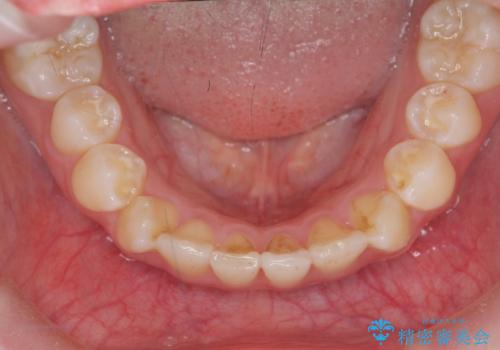

インビザラインライトで行う短期マウスピース矯正治療

- 前歯のガタつきを並べたいたいと、矯正治療を希望され来院されました。

とにかく短期間で前歯だけの治療を行いという希望が強く、全体矯正と前歯だけの部分矯正の仕上がりのイメージを確認したのち14枚のマウスピースで前歯のみの矯正治療を行っていくこととしました。

インビザラインライトは軽度なガタつきや傾斜の改善に用いられる全14枚のマウスピース矯正です。

短期間で治療の終了が見込めるだけでなく、料金もインビザラインフルに比べリーズナブルです。